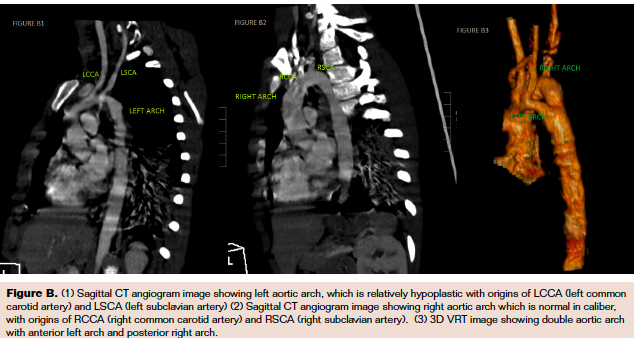

Her physical examination and electrocardiogram results were essentially unremarkable. Chest x-ray was suggestive of right aortic arch with consolidation in the right lower zone. Echocardiogram did not reveal any intracardiac lesion but raised suspicion of abnormality of aortic arch—presence of 4 neck vessels instead of the typical 3 vessels. Computed tomography (CT) angiogram was subsequently done, and it revealed the presence of double aortic arch (Figure A), with a larger right-sided arch (blue arrow) and smaller left arch (green arrow) joining to form the descending aorta (grey arrow). The right subclavian and common carotid arteries arose from the right arch (Figure B2) and, similarly, left subclavian and common carotid arteries from the left arch (Figure B1). A sudden taper (blue arrow in Figure C2) in the esophageal caliber was noted, suggesting esophageal compression, which may have exacerbated the respiratory symptoms.